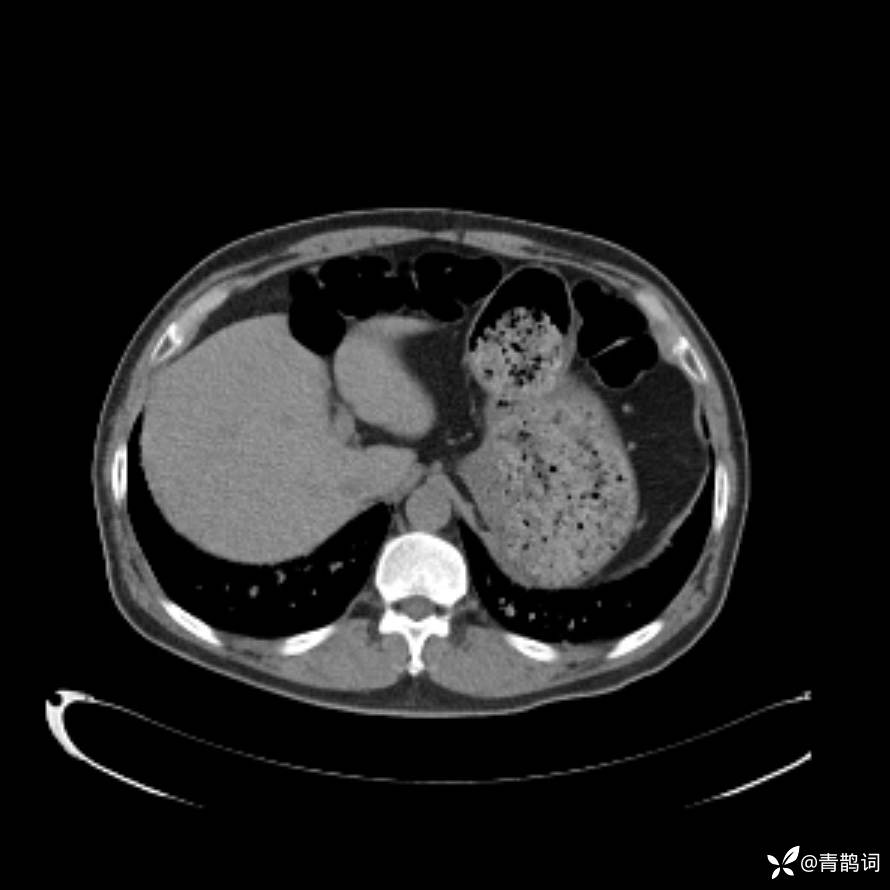

患者年龄:30岁。

患者性别:男。

简要病史:左颜面部肿胀2年,反复咳嗽咳痰,逐渐加重。

辅助检查

结合病史及影像学表现,期待评论区各位老师各抒己见~